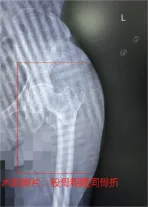

拍片结果显示,刘阿婆左侧大腿骨头(股骨粗隆)骨折了!随后,刘阿婆被迅速转入创伤骨科由主任医师胡海澜带领团队进行进一步治疗,并等待术前会诊。

经过初步评估,医生发现刘阿婆存在血压偏高、中重度骨质疏松等多种基础疾病。面对这一复杂情况,团队迅速进行多学科会诊,最终确定了治疗方案——为刘阿婆使用先进的PFNA(防旋股骨近端髓内钉)进行“左侧股骨骨折闭合复位内固定术”。PFNA创伤更小、操作更简单、设计更符合解剖学和生物力学,是目前治疗股骨粗隆间骨折的优选方案。